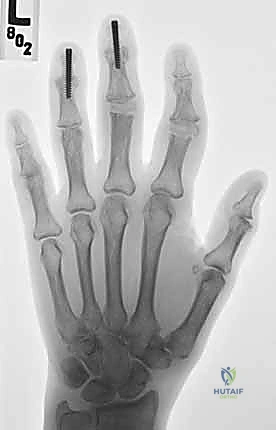

تُجرى هذه العملية تحت التخدير الموضعي (إحصار العصب) أو التخدير العام، وتستغرق عادة من ساعة إلى ساعتين للمفصل الواحد، وقد تطول إذا تم استبدال عدة مفاصل في نفس الوقت. إليكم الخطوات الجراحية كما يجريها د. هطيف ببراعة:

4. إدخال مفصل السيليكون (المُباعِد)

يتم إدخال مفصل السيليكون المعقم بحذر شديد. يتم إدخال أحد طرفيه في العظمة الدانية والطرف الآخر في العظمة القاصية. المفصل مصمم لينثني من المنتصف مع حركة الإصبع.

5. اختبار الاستقرار والحركة (Intraoperative Testing)

عانت السيدة مريم من التهاب المفاصل الروماتويدي لسنوات طويلة، مما أدى إلى انحراف شديد في أصابع يدها اليمنى وألم يمنعها من إعداد الطعام لأسرتها. بعد زيارتها لعيادة الأستاذ الدكتور محمد هطيف في صنعاء، تم التخطيط لإجراء استبدال لأربعة مفاصل (MCP) بالسيليكون في عملية واحدة. اليوم، وبعد 6 أشهر من الجراحة والتأهيل، عادت يد مريم مستقيمة، اختفى الألم تماماً، وعادت لتمارس هوايتها في الخياطة والطبخ بابتسامة لم تفارق وجهها.